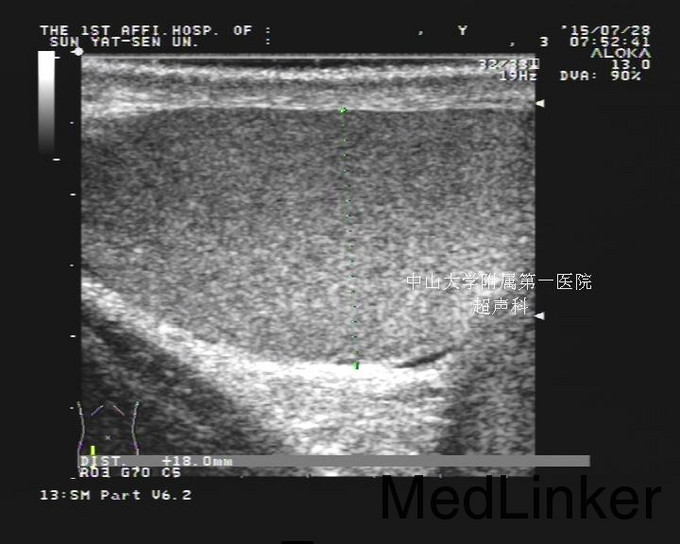

查体:阴茎体中部6点方向可扪及结节样瘢痕,余未及明显异常。 睾丸、附睾+精索静脉彩超:检查结论/诊断:双侧未见精索静脉曲张。双侧睾丸及附睾超声检查未见异常。